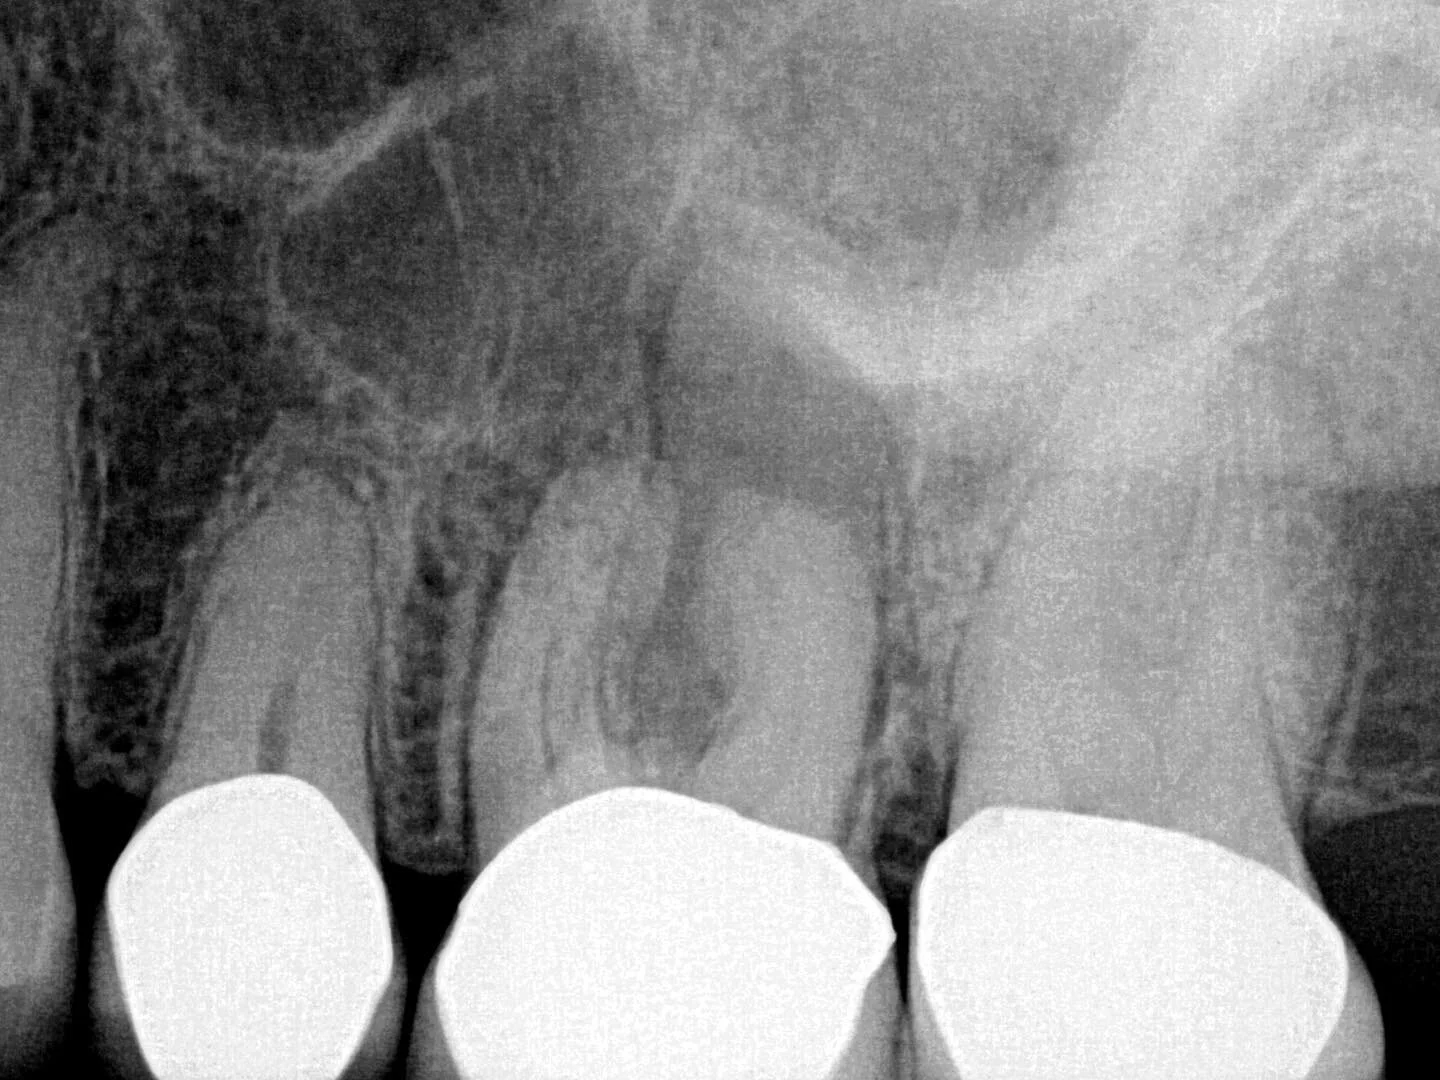

Dr. Zegar’s endodontic cases portfolio :